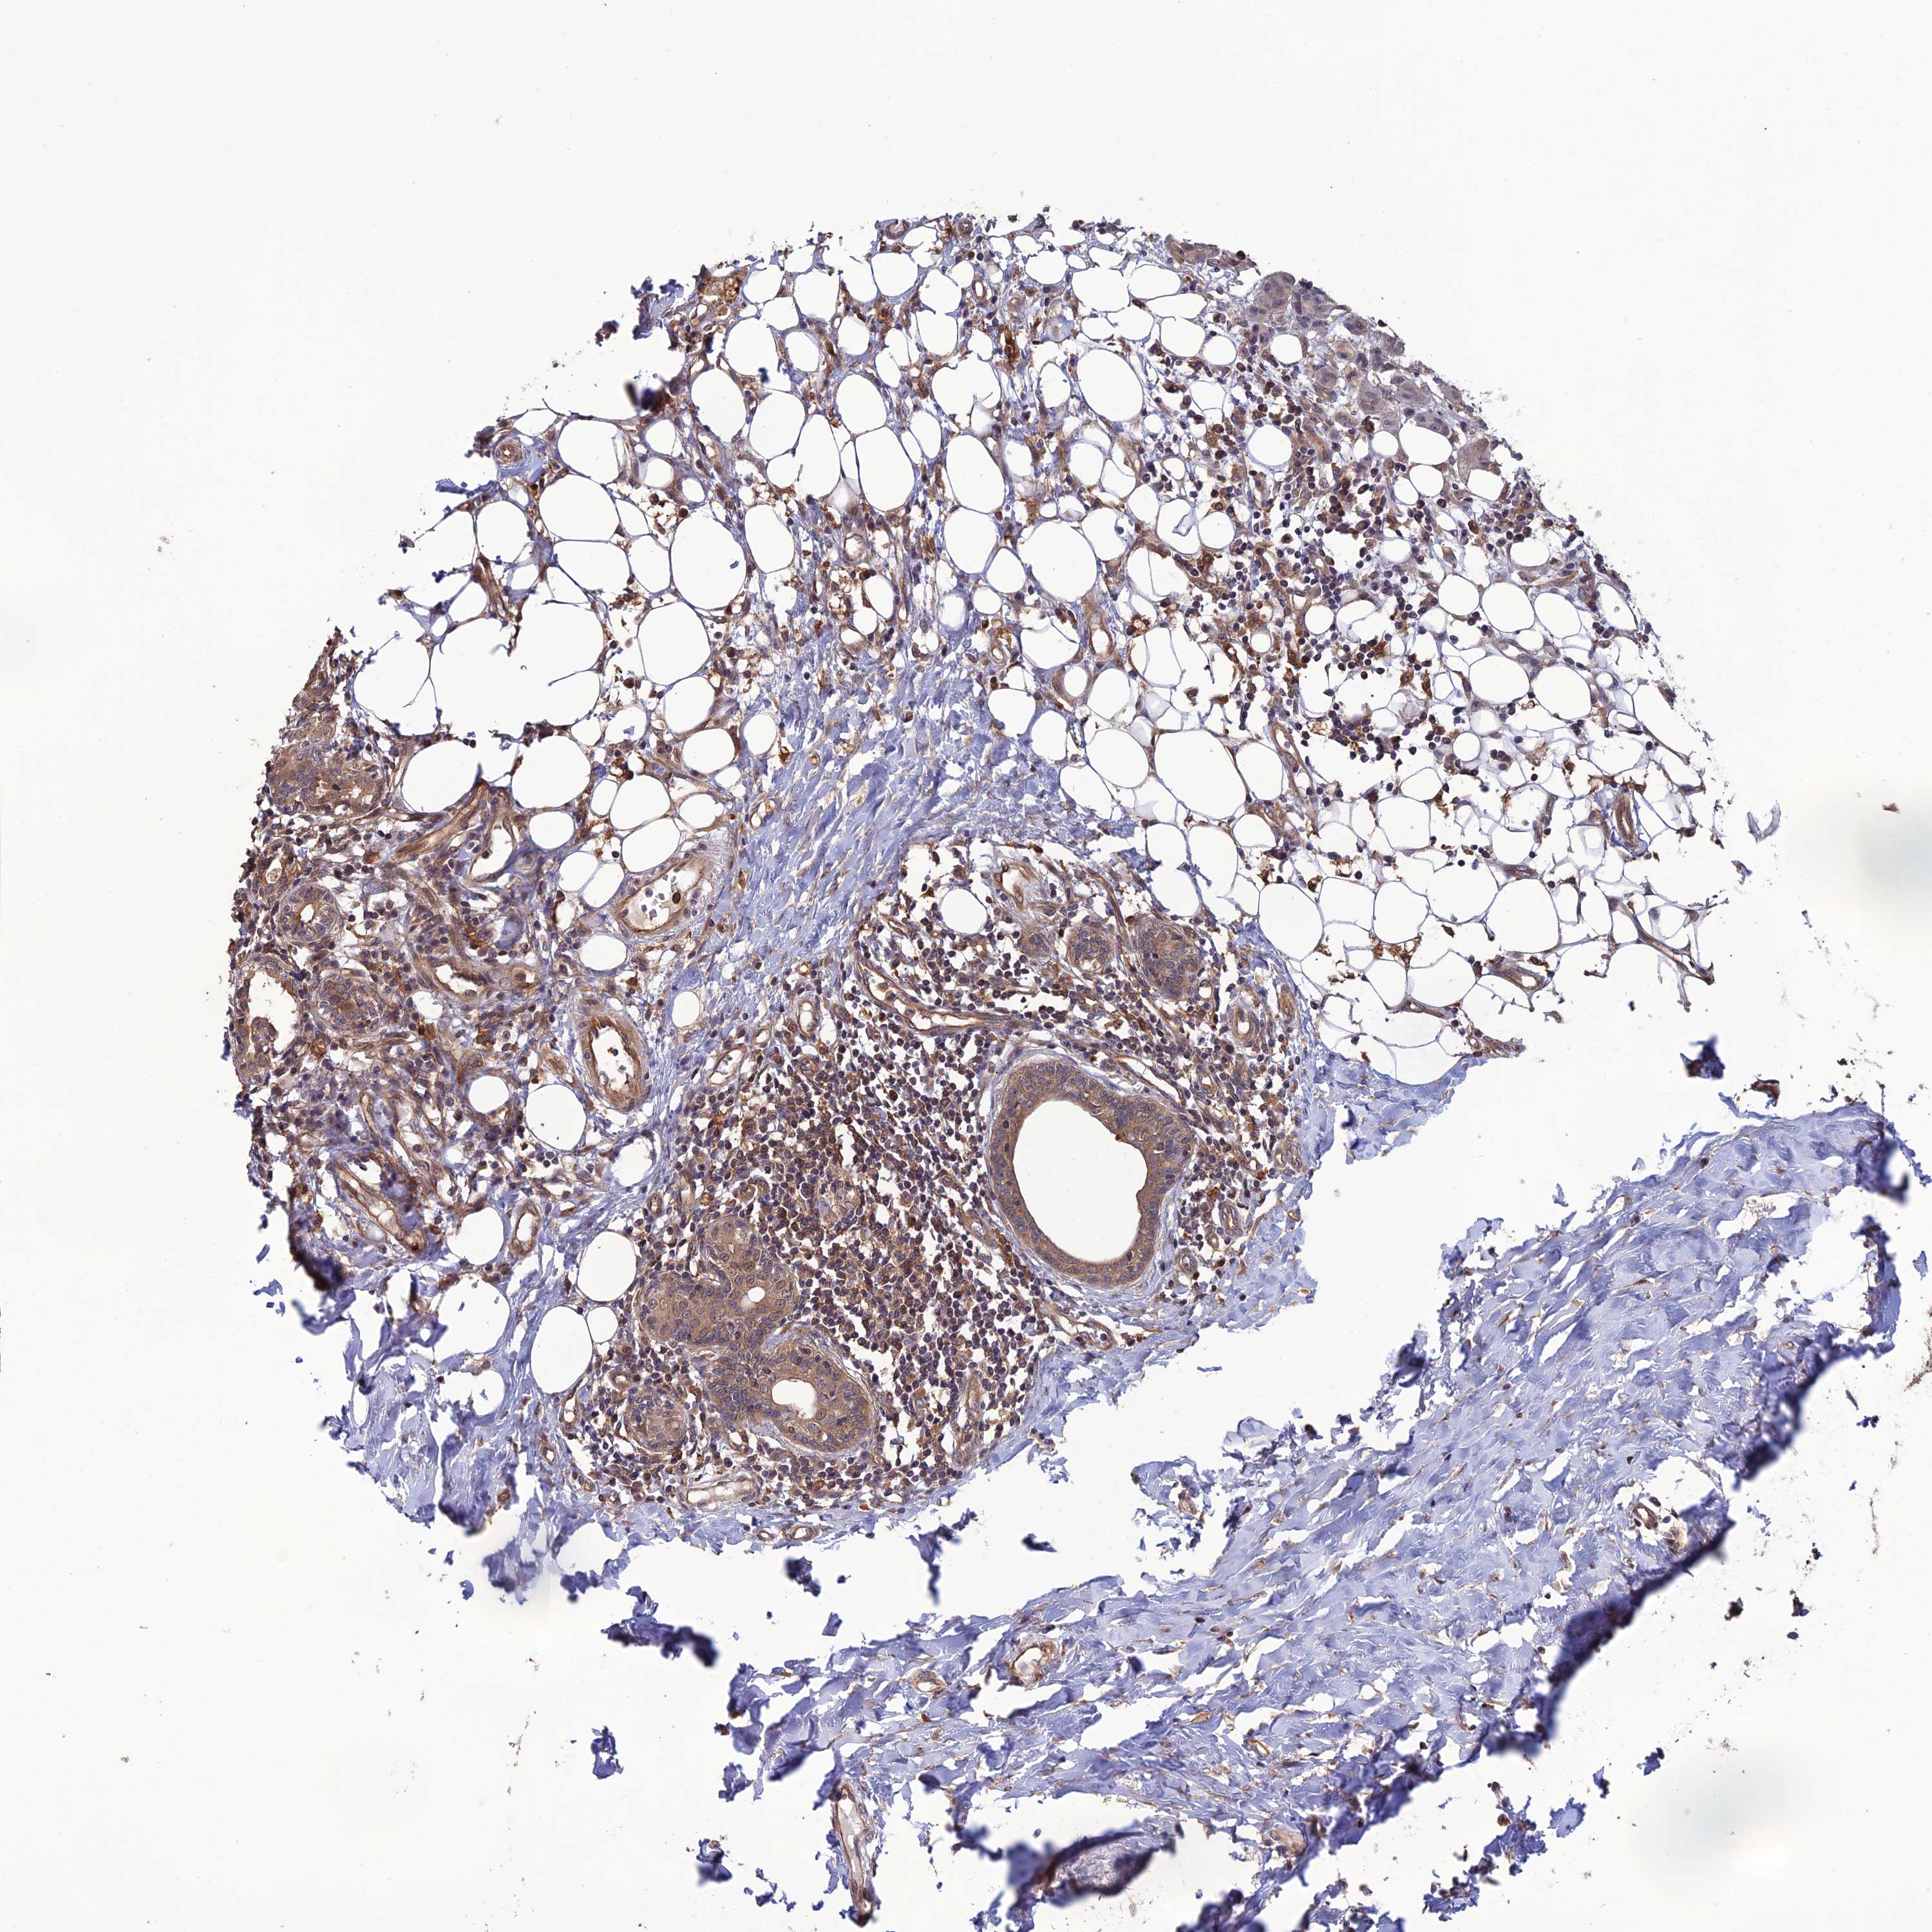

BRCA TCGA BRCA VALIDATION PROTEIN EXPRESSION